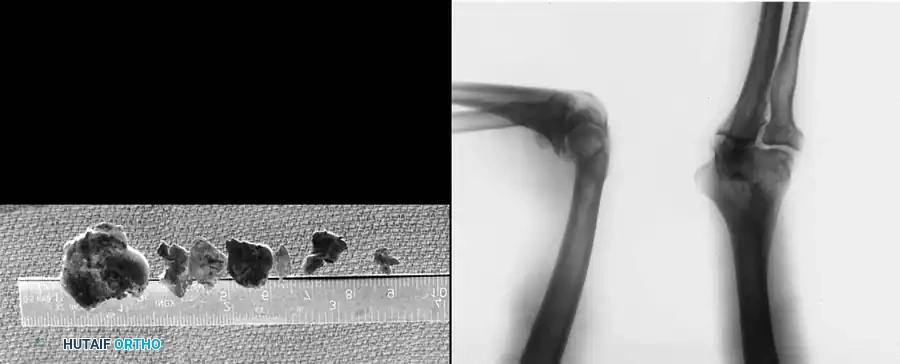

- Loose Body Removal: Evaluation and extraction of chondral or osteochondral loose bodies, which frequently reside in the olecranon or coronoid fossae.

- Inflammatory Arthropathy: Partial or subtotal synovectomy, which is particularly beneficial in patients with rheumatoid arthritis or synovial chondromatosis.

Postoperative Protocols and Rehabilitation

At the conclusion of the procedure, the joint is thoroughly irrigated to remove any remaining debris. The portals are typically closed with simple interrupted non-absorbable sutures or sterile adhesive strips, depending on the size of the cannula used.

A bulky, sterile compressive dressing is applied to minimize postoperative swelling and hemarthrosis. The neurovascular status of the extremity must be documented immediately in the recovery room.